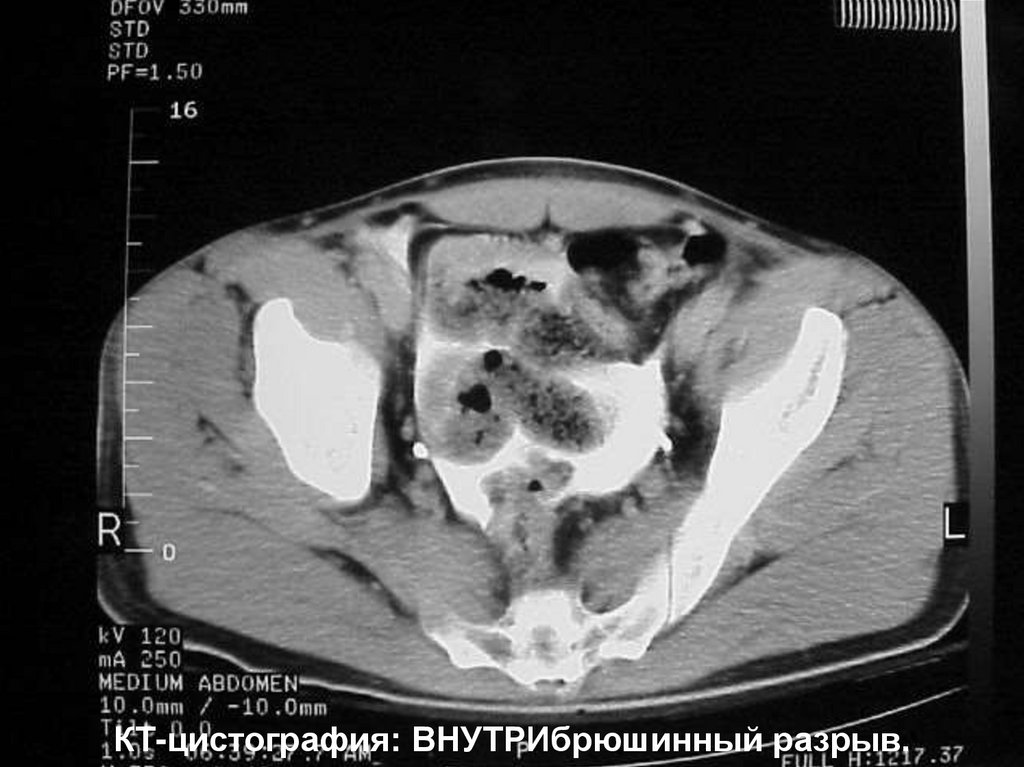

84.

КТ-цистография: ВНУТРИбрюшинный разрыв.